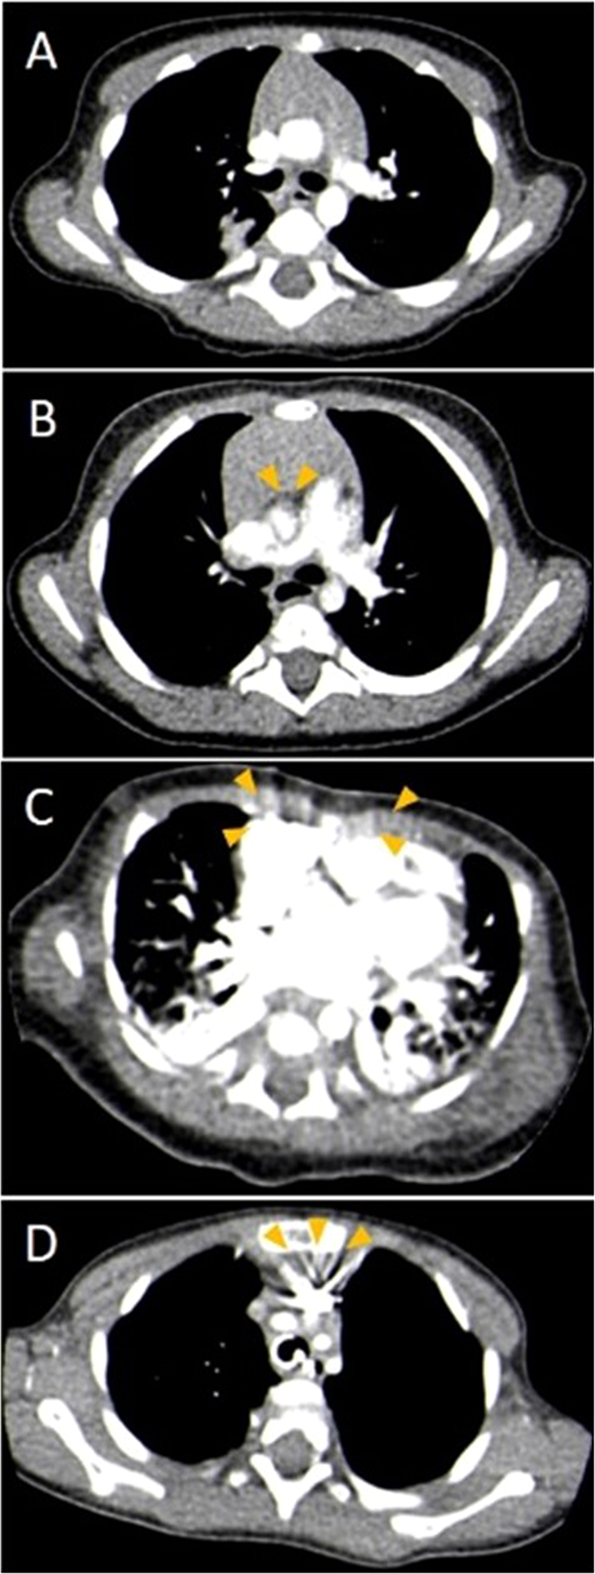

Image quality and CA related image artifacts were visually graded by two of the authors (E.N., S.T.) in consensus. A five-grade Likert scale was used for general image quality: score 1, excellent; score 2, good; score 3, acceptable; score 4, poor; and score 5, bad. To complete the assessment, we separately applied a four-grade Likert scale system exclusively for the analysis of CA-related image artifacts: score 1, no artifacts; score 2, minor artifacts; score 3, major artifacts; score 4, marked image noise and extensive image blurring (Fig. 3).

All of the examinations were diagnostic after adjusting the window settings. Even in case overall image quality assessment yielded grades 4 or 5, the clinical question could have been answered and no measurement was needed to be repeated. At the assessment of general image quality (Table 4), significantly higher scores were found in group I over group II and III (p = 0.020). Evaluation of CA- related artifacts revealed the same findings (p = 0.006). None or only minor artifacts were caused by CA in 78% of the examinations with MBT, while this ratio was 52% in group II and 47% in group III. Noteworthy, that in group I, only 3% were graded with image quality score 4, while image quality score 4 or 5 resulted in 18% of the cases in group II and 33% of the cases in group III.